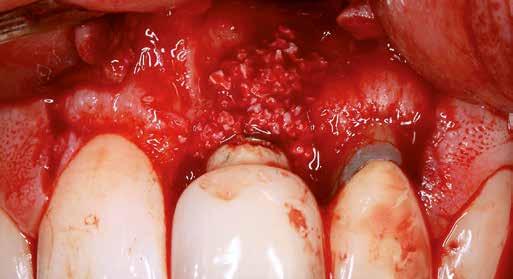

Sebészi technika

Helyi érzéstelenítést végeztünk a műtéti területen artikain és 1:100 000 adrenalin segítségével. A recipiens területet előkészítettük, élesen disszekciót végeztünk, hogy egy izomtapadástól mentes periosteum ágyat képezhessünk. Ettől disztálisan két párhuzamos parakresztális metszést végeztünk egy 15C-s szikepengével, majd a metszéseket egy

2–5. ábra: A metszések és a deepitelizáció. – 6–9. ábra: Félvastag lebeny. – 10. ábra: A nyelezett ínylebeny „bepróbálása”.

horizontális metszéssel kötöttük össze (2–5. ábra). A metszések hosszát és a köztük lévő távolságot minden esetben a lágyszövet augmentációhoz szükséges keratinizált szövet határozza meg. A lebeny deepitelizációját egy 15C-s szikepengével végeztük (6. ábra). Ezt követően félvastag lebenyt preparáltunk (7. ábra). A lebenyt apikálisan, az alapjáról belső, felületes metszéssel felszabadítottuk, hogy passzívan áthelyezhessük és rögzíthessük, feszülés nélkül. Meziális irányba 180 fokkal átforgattuk (8–9. ábra). A meziális papillát alagúttechnikával (tunnelling technique) készítettük elő a graft befogadására (10. ábra). Az így kialakított lebenyt a recipiens ágyban rögzítettük az újonnan kialakított vesztibulum alapjánál 5-0 nem felszívódó PTFE (Coreflon, IMPLACORE) varratokkal. A graftot behajtottuk az ínyszél alá és meziális oldalon rögzítettük PTFE varratokkal (11–14. ábra) A műtétet követően napi kétszeri, 0,12%-os klórhexidin tartalmú szájvízzel történő öblögetést javasoltunk a páciensnek, két héten keresztül. Gyulladáscsökkentésre 8 óránként 400 mg Ibuprofént javasoltunk, három napon keresztül. A páciens elmondása szerint sem fájdalmat, sem különösebb diszkomfortot nem tapasztalt. Ezt követően, további 4 héten keresztül, 0,2%-os klórhexidin tartalmú szájvízzel történő öblögetést javasoltunk a betegnek és instruáltuk, hogy lehetőleg ne mossa fogkefével az érintett területet. A varratokat egy héttel később távolítottuk el. A donor és a recipiens terület – 10 nappal a műtétet követően – kiválóan gyógyult (15–16. ábra). Az ezt követő kontrollokat a következő időpontokban ejtettük meg: kettő, illetve négy héttel a műtét után, majd három, hat és tizenkét hónappal később, ezt követően pedig félévente (17–20. ábra). Minden kontroll alkalmával professzionális fenntartó kezelést végeztünk a területen.